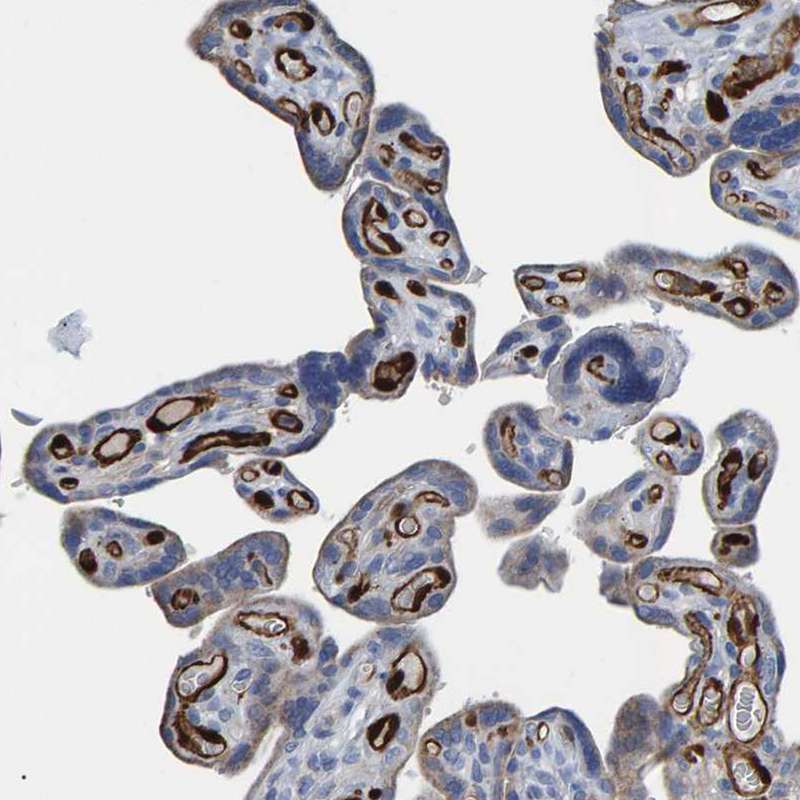

Immunohistochemistry analysis in human placenta and cerebral cortex tissues using HPA023072 antibody. Corresponding IDO1 RNA-seq data are presented for the same tissues.